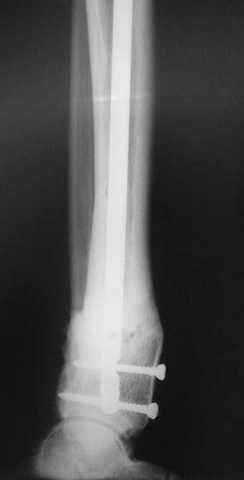

7, 8, 9, 10, 11 - через 8 мес после травмы перелом сросся.

Пациент ходит без дополнительной опоры, не хромает (видеоролик выложил сюда

http://rapidshare.com/files/14134274/Patient_B.AVI.html, вес 892 кб).